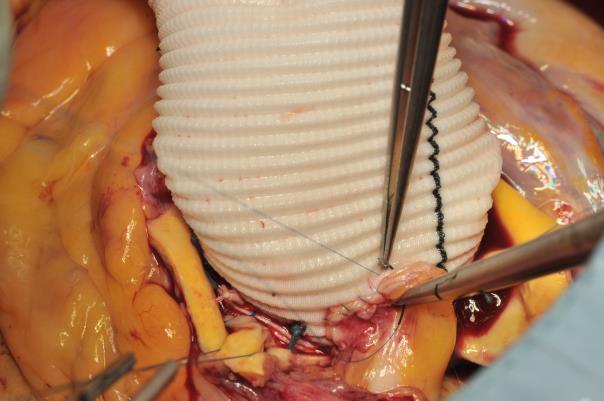

The procedure starts with the proximal suture of the composite graft prosthesis to the aortic annulus using separated mattress suture of 2.0 Ethibond backed with small Teflon pledgets. The first suture is placed at the level of the commissure between the left and right coronary sinuses and the following are stitched in a clockwise fashion (Image 1). The sutures are placed through the annulus with the pledgets left either on the aortic side thus everting the annulus, but in small annular diameters. The author prefers to stich these sutures from the ventricular side to the aorta, therefore the pledgets lie under the aortic annulus. Then the sutures are placed through the sewing ring of the composite graft prosthesis (Image 2) which is later on parachuted down to the aortic annulus (Image 3). The sutures are then tightened and the valve is placed into the outflow tract of the left ventricle (this provides excellent hemostasis).

Image 1: Suturing the composite graft to the aortic annulus starts at the level of the commissure between the left and right coronary sinuses and is continued clockwise in back-end fashion up to the middle of the non-coronary sinus. Thereafter fore-hand technique is applied for the rest of the non-coronary sinus and the left coronary sinus.